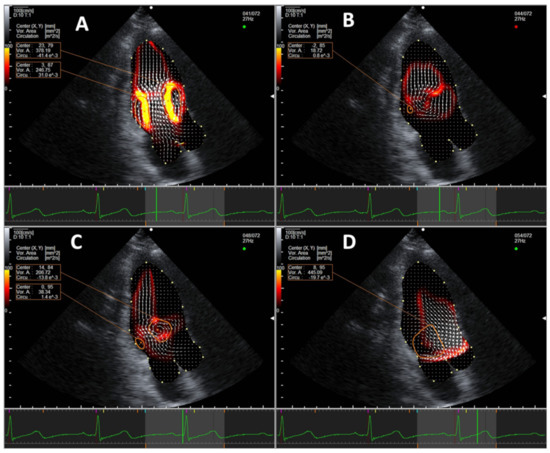

3.1. Normal Intracardiac Vortex Flow and EL

3.2. Intracardiac Vortex Flow Characteristics and Aging